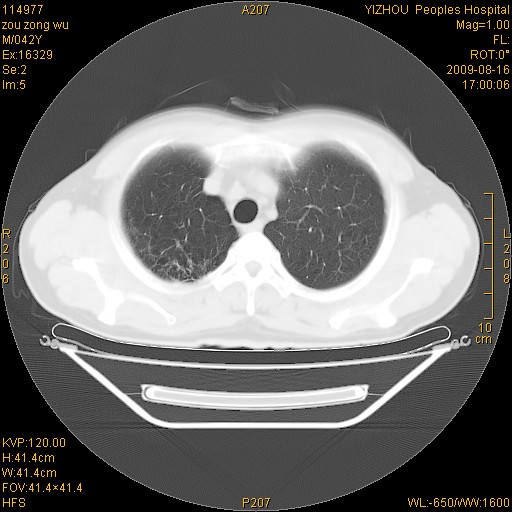

以下是引用zjzjr在2009-8-17 10:42:00的发言:[br]右侧间质性肺炎伴纤维化,右肺下叶肺囊肿伴感染(不除外外伤后引起),右肺野及胸壁软组织\\肝内见多发斑点状,中枪了吧.右侧胸膜肥厚\\粘连.